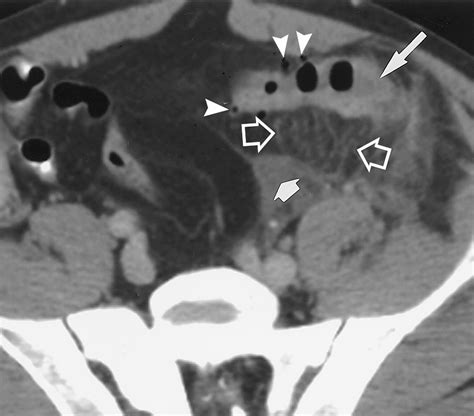

Case Study 1: Appendicitis

A 25-year-old patient presents with right lower quadrant pain, nausea, and fever. A CT scan reveals fat stranding in the right lower quadrant, appendiceal thickening, and periappendiceal fluid. These findings are consistent with appendicitis, and the patient undergoes an appendectomy.

Appendicitis CT Scan